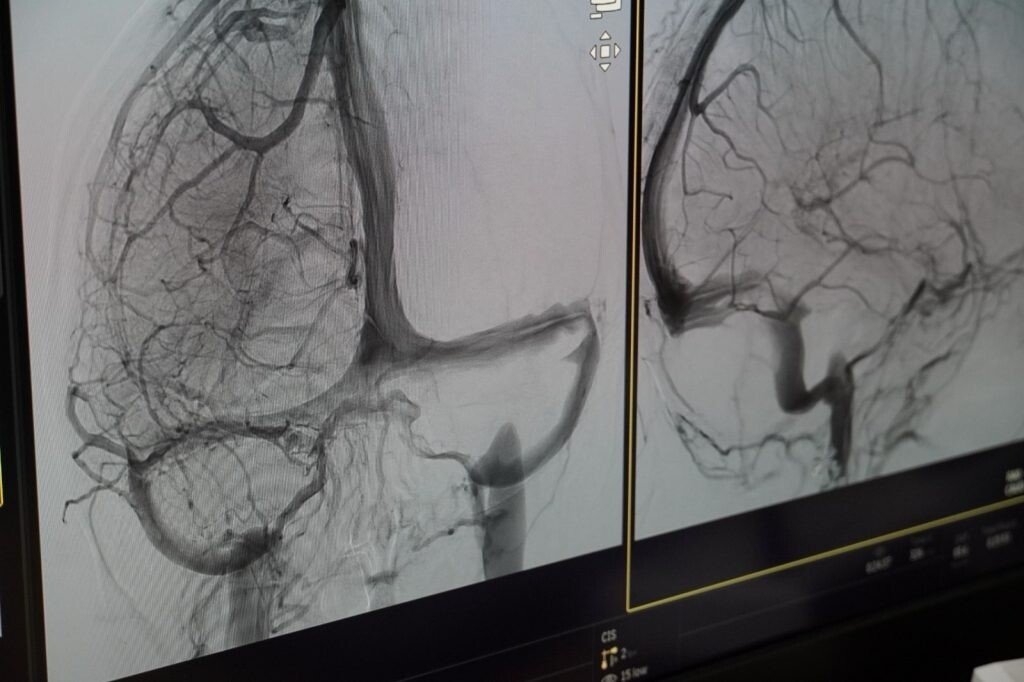

„De la începutul acestui an, am intervenit în 28 de cazuri, dublu față de aceeași perioadă a anului trecut, iar rata de reușită în privința eliminării cheagurilor de sânge a depășit 90%. Cu banii primiți acum, avem posibilitatea să efectuăm până la 100 de intervenții”, a declarat dr. Monica Mănișor, neuroradiolog intervenționist, și medic coordonator al Compartimentului de Radiologie și Imagistică Medicală Neurologie.

„Ca să ajungem în această fericită situație, de a avea un centru de tratare AVC, a trebuit, în primul rând, să reabilităm și să modernizăm spațiile medicale, apoi să achiziționăm aparatura necesară. Aici, la Sibiu, prin fonduri europene nerambursabile am adus tehnică medicală de ultimă generație, printre care și un angiograf performant, utilizat în intervențiile AVC, a cărui valoare a depășit 7 milioane de lei. Am avut și șansa ca doamna dr. Monica Mănișor, sibiancă la origine, să aleagă spitalul nostru, după ce a profesat o lungă perioadă la Spitalul Universitar din Strasbourg”, a declarat Daniela Cîmpean, președinta Consiliului Județean Sibiu.